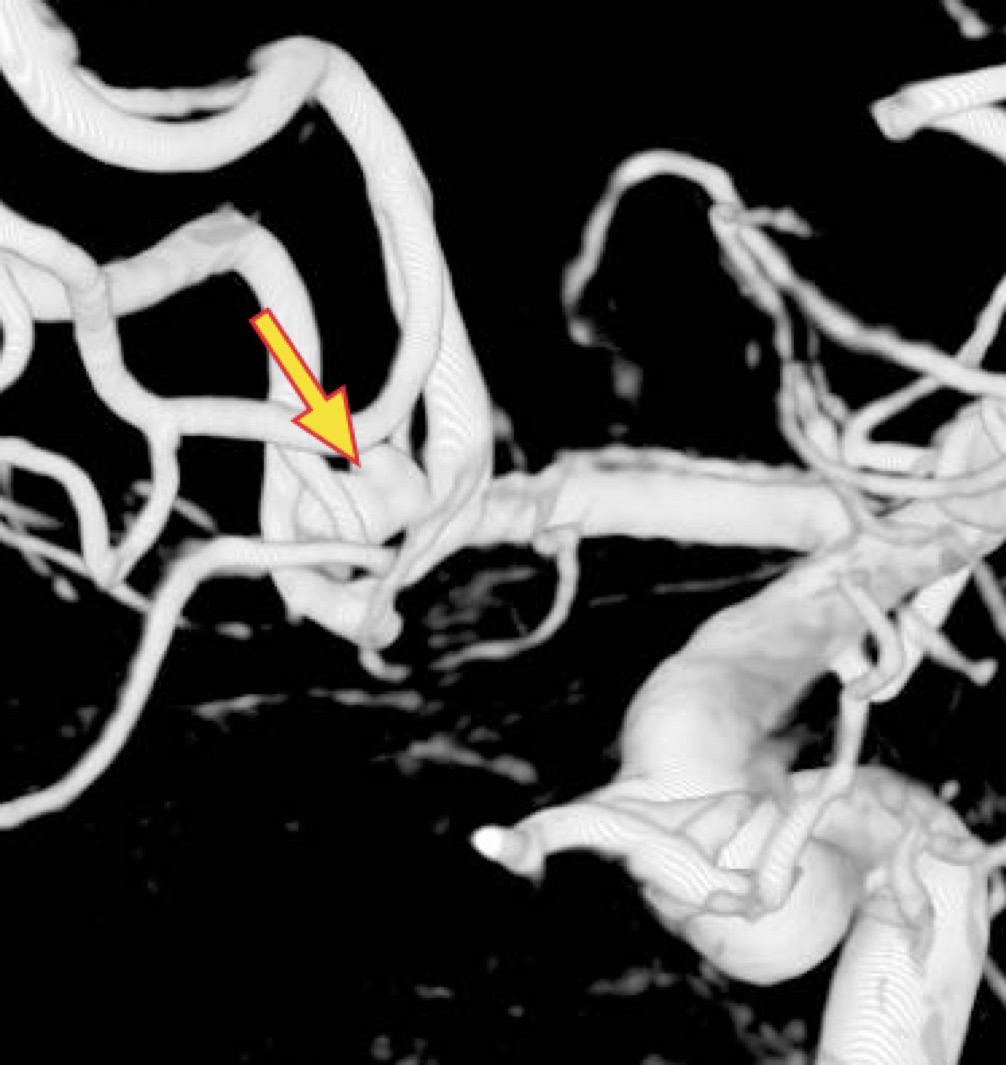

<クリッピング前>矢印は動脈瘤

<クリッピンング後>矢印はクリップ

<3DCTA:コイル塞栓前>

矢印は動脈瘤

<3DCTA:コイル塞栓後>

矢印は動脈瘤の消失を示す